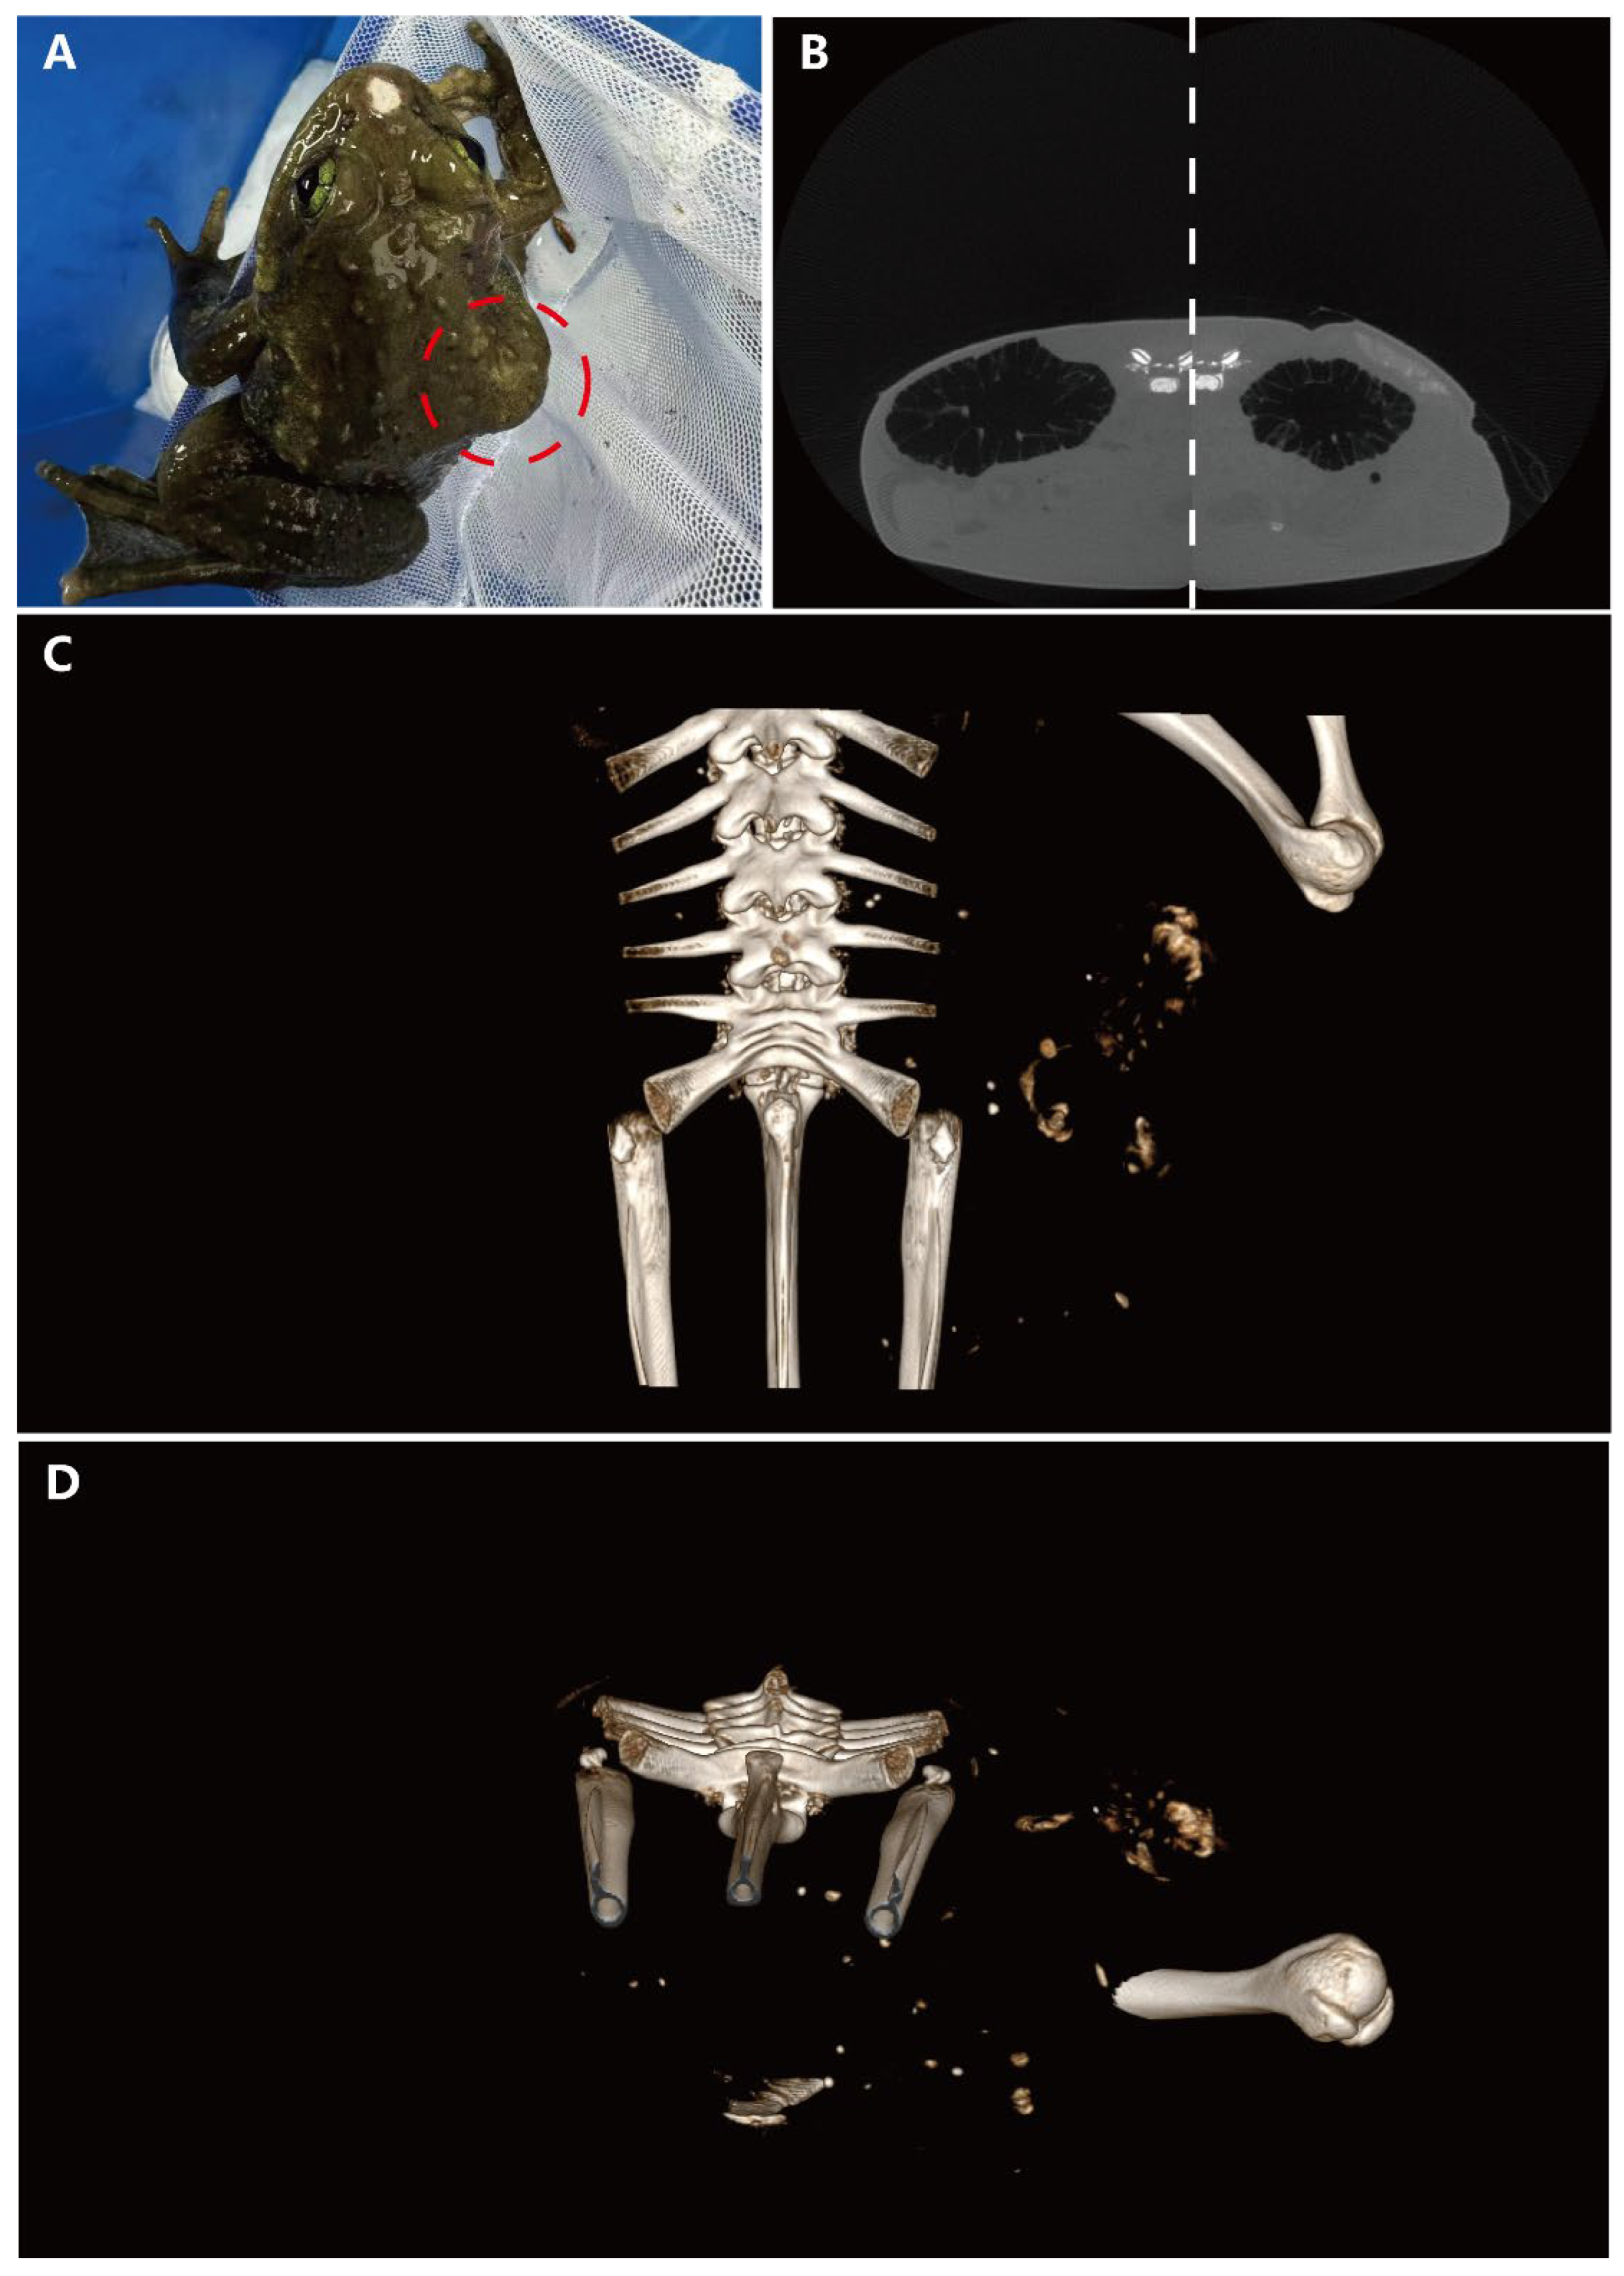

On gross examination, a subcutaneous bulge was observed on the right dorsoventral surface of the frog, along with a mechanical injury at the rostral end (Figure 1A). Micro-CT scans were performed, revealing a region with relatively clear edges but a complex internal structure on the dorsal side of the body cavity, compared to the healthy side. This finding indicated uneven tissue composition in the affected region. Notably, a circular, uneven mass of similar density was also found on the liver (Figure 1B). The spatial relationships of these masses were further illustrated using three-dimensional imaging techniques. The general shape of the largest dorsoventral mass was viewed from the dorsal angle, demonstrating its irregular structure (Figure 1C). Additionally, a cross-sectional image of the body cavity revealed that the nodular mass was dispersed in multiple locations within the cavity, suggesting significant heterogeneity and potential aggressiveness (Figure 1D).

Figure 1. Gross examination and micro-CT scan results. (A) Subcutaneous mass visible in the red circle on the right dorsoventral surface. (B) CT scan comparison between the diseased and healthy sides (the image is composed of two control images spliced with dotted lines). (C) 3D model illustrating the spatial relationships of the mass. (D) Horizontal cross-section of the body cavity revealing dispersed nodular masses.